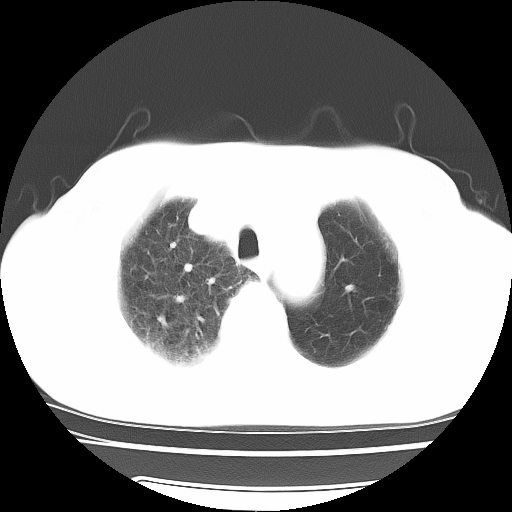

男,71岁,咳嗽,气喘10年,再发并咯血.胸片见气胸

考虑  左肺中心型肺癌伴阻塞性肺炎,肺不张,纵膈淋巴结肿大。慢支炎,肺气肿,左侧气胸肺压缩5%

左侧中央型肺癌伴纵膈淋巴结转移。

左肺中心型肺癌伴阻塞性肺炎,肺不张,纵膈淋巴结肿大

1)考虑左肺中心型肺癌伴阻塞性肺炎、左肺下叶肺不张、左侧肺气肿,纵膈淋巴结转移。2)左侧气胸(肺组织压缩约5%)。

左肺中心型肺癌伴阻塞性肺不张、肺气肿 。

1)考虑左肺中心型肺癌伴阻塞性肺炎、左肺下叶肺不张、左侧肺气肿,纵膈淋巴结转移。2)左侧气胸。